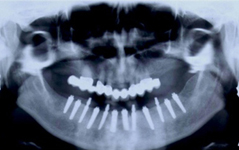

• Zavedení implantátu do kosti čelisti

Bezzubá čelist je hlavní indikací pro ošetření pomocí implantátů. Zejména celkové zubní náhrady v dolní čelisti mají velice nízkou stabilitu a držení díky velkému úbytku kosti.

S pomocí zubních implantátů můžeme díky různým kotevním systémům (třmeny, kulové hlavy, Locatory) zajistit stabilitu a držení protézy nebo při použití většího počtu implantátů zhotovit pevné náhrady – můstky nalepené nebo našroubované na pevno na implantáty.

Zavedení implantátů do kosti je většinou ambulantní chirurgický výkon, srovnatelný s vytržením zubu a většinou se provádí v lokální anestézii. Ve výjimečných případech je možné použít i analgosedaci či celkovou narkózu. Operaci provádí zubní lékař-implantolog při dodržení všech podmínek sterility pro operaci. Nástroje pro tuto operaci jsou konstruovány tak, aby výkon byl šetrný vůči kosti a zavedení implantátu bylo provedeno ve velmi krátké době. Díky kvalitní anestézii je výkon nebolestivý. Aby byl pooperační otok co nejmenší, je potřeba operovanou oblast chladit, dle poučení ošetřujícího lékaře. Lékař také ordinuje podle potřeby léky na bolest, případně antibiotika.